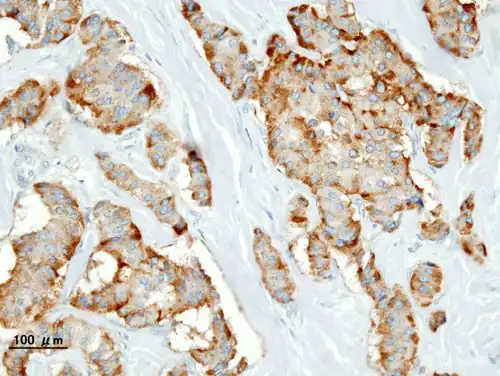

Chromogranin A

Insulin immunostain